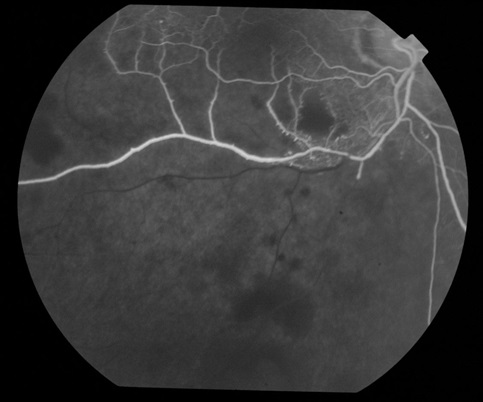

Локализованный интра- или экстрацеллюлярный отек сетчатки и периваскулярный экссудат могут сдавливать сосуды и вызывать выраженные изменения гемоциркуляции в них вплоть до полного стаза. Если кровоток в сосуде сохранен, он может быть узким, иногда, прерывистым, но прослеживается как дистальнее, так и проксимальнее зоны ретинального отека и периваскулярного экссудата. При полной облитерации сосудов ток крови в них исчезает и, тогда они выглядят в виде белых полос. На ангиограммах, при поражении сосудистой системы сетчатки, может наблюдаться изменение последовательности фаз, неравномерность заполнения флюоресцеином сосудов, контрастирование сосудистой стенки и флюоресценция окружающей области за счет экстравазального выхода флюоресцеина в результате нарушения проницаемости.

При офтальмоскопировании ишемические зоны не видны, на их существование косвенно могут указывать облитерированные сосуды, некоторая бледность и локальная отечность сетчатки. Нередко неперфузируемые области сетчатки окружены расширенными сосудами и микроаневризмами. Только флюоресцентная ангиография позволяет определить и четко локализовать ретинальные ишемические зоны. На флюоресцентных ангиограммах они выглядят в виде темных, серых, нефлюоресцирующих или гипофлюоресцирующих участков сетчатки, часто окруженных расширенными флюоресцирующими, с экстравазальным выходом контраста сосудами и микроаневризмами по краям ишемии. Ишемические зоны являются предвестниками неоваскуляризации, которая может развиваться на диске, сетчатке или радужке.